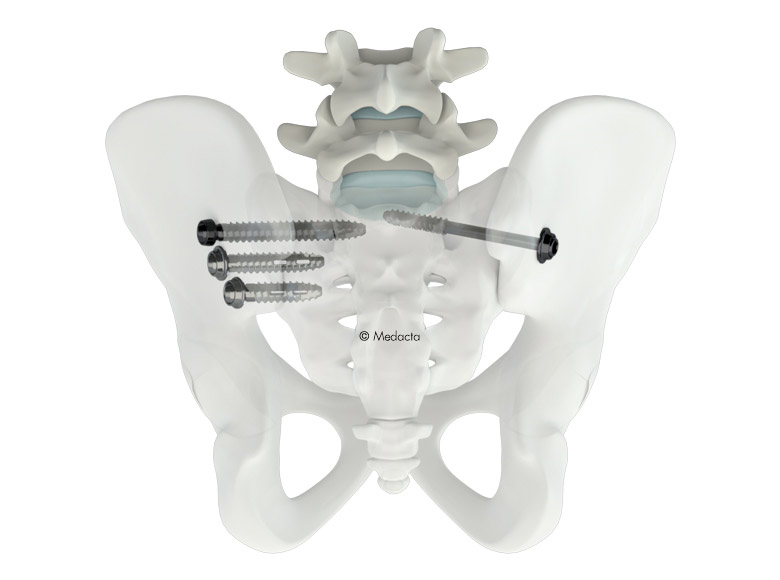

The OZARK Cervical Plate Systems are available in two designs, OZARK Guide and OZARK View, both featuring an advanced per-level, integrated locking cover that provides surgeons with clear visual and tactile confirmation of the final lock position. They both include a full range of plate and screw sizes and instrumentation for creating constrained, semi-constrained or hybrid screw constructs. The systems are compatible with K2M’s CASCADIA™ Cervical 3D Interbody Systems featuring Lamellar 3D Titanium Technology™, which uses an advanced 3D printing method to create structures that are impossible with traditional manufacturing techniques.

Balance ACS® or (BACS®) is a comprehensive platform applying three-dimensional solutions across the entire clinical care continuum to help drive quality outcomes in spine patients. BACS provides solutions to help surgeons achieve balance of the spine by addressing each anatomical vertebral segment with a 360-degree approach to the axial, coronal, and sagittal planes, emphasizing Total Body Balance as an important component of surgical success.

K2M Group Holdings, Inc. is a global leader of complex spine and minimally invasive solutions focused on achieving three-dimensional Total Body Balance. Since its inception, K2M has designed, developed, and commercialized innovative complex spine and minimally invasive spine technologies and techniques used by spine surgeons to treat some of the most complicated spinal pathologies. K2M has leveraged these core competencies into Balance ACS, a platform of products, services, and research to help surgeons achieve three-dimensional spinal balance across the axial, coronal, and sagittal planes, with the goal of supporting the full continuum of care to facilitate quality patient outcomes. The Balance ACS platform, in combination with the Company’s technologies, techniques and leadership in the 3D-printing of spinal devices, enable K2M to compete favorably in the global spinal surgery market. For more information, visit www.K2M.com and connect with us on Facebook, Twitter, Instagram, LinkedIn and YouTube.